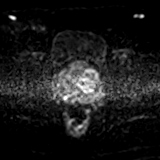

轴位

DWI

4.jpg

ADC

5.jpeg

前列腺增大,大小为52 x 56 x 57 mm(体积87 ml)。

PSA 7.279 ng/ml,PSA密度0.084 ng/ml/cc。

在前列腺中部/尖部,右侧外周带/周围膜交界处可见一大小为7 x 5 mm的毛刺状、边界不清的T2低信号病灶,伴有扩散受限和早期动脉期强化,提示为PI-RADS 4级病灶。